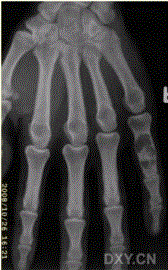

问题 患者男,28岁,偶尔发现右手第5近节指骨肿胀。查体:右手掌肿块,质硬,无明显压痛,无发热。进行了右手X线平片CT检查(下图)。 此病变最可能的诊断是

选项 A.骨囊肿 B.内生软骨瘤 C.骨结核 D.成软骨细胞瘤 E.骨巨细胞瘤

答案 B